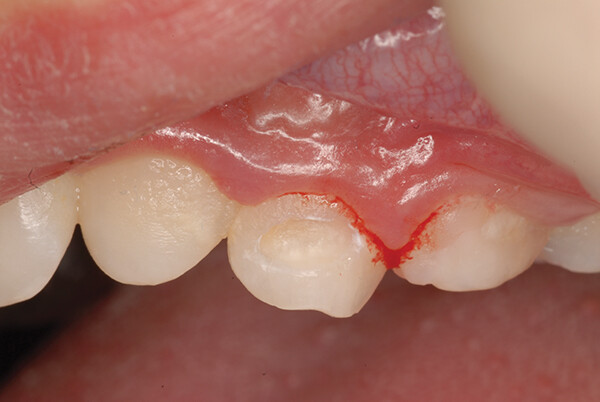

Случай 2: EQUIA Forte HT Fil на зубе № J

Кариес присутствовал в дистальной лунке зуба № J (рис. 4). Поскольку при использовании EQUIA Forte HT Fil не требуется адгезив, визиты к стоматологу для пациентов детского возраста могут быть короче. Кроме того, способность материала высвобождать фтор в эмаль и дентин полезна для всех детских пациентов, но особенно для тех, кто подвержен риску развития кариеса.